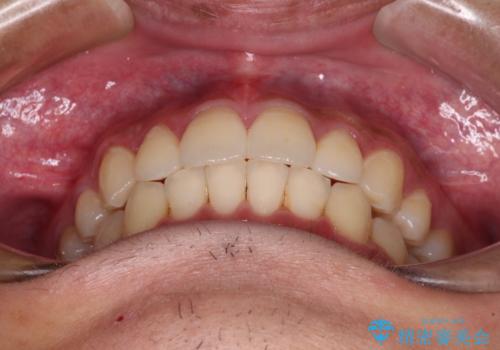

矯正治療後は、再度後戻りすることを極力回避するために、下顎前歯の舌側を細いワイヤーを用いて保定することとしました。